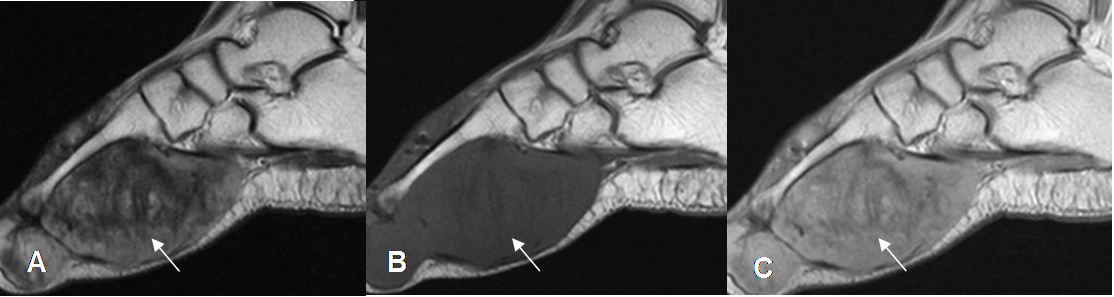

Fig 113 B. Fibromatosis plantar gigante.

A: RM sagital en T2. Imagen ovalada en la planta del pie, hipointensa en T2, por la presencia de tejido fibroso.

B: RM sagital en T1 simple y C: RM T1 con contraste. Lesión hipointensa, que realza fuertemente con el contraste.